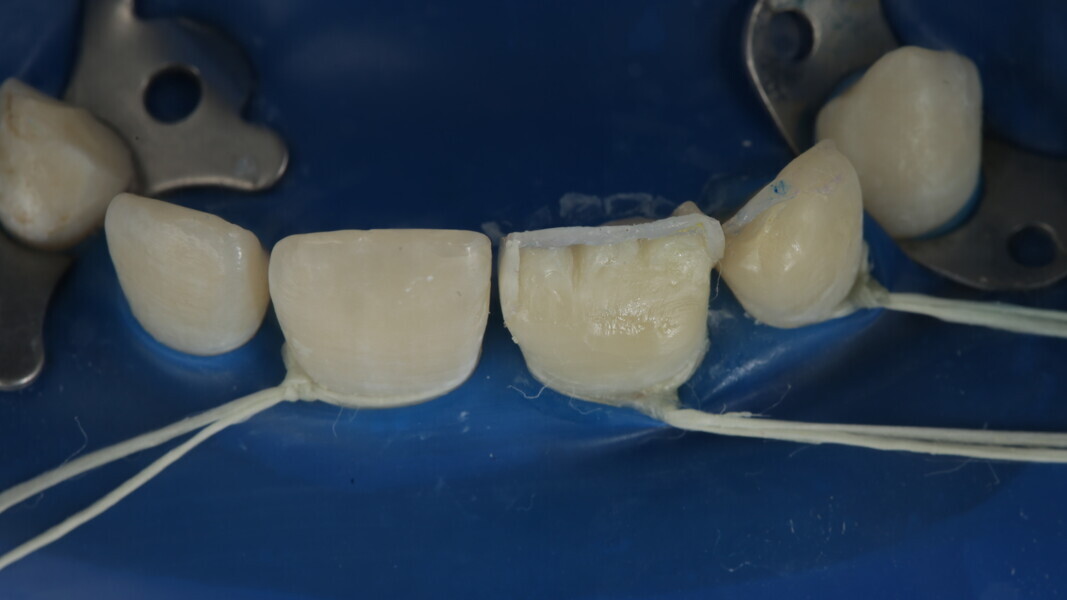

Fig 25-30: Layering protocol step by step